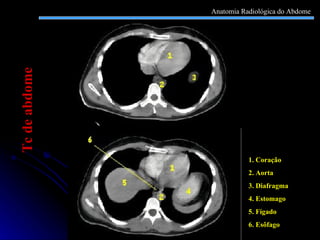

1. Coração 2. Aorta 3. Diafragma 4. Estomago 5. Fígado 6. Esôfago Tc de abdome Anatomia Radiológica do Abdome

1. Coração 2.Aorta 3. Diafragma 4. Estomago 5. Fígado 6. Esôfago Tc de abdome Anatomia Radiológica do Abdome